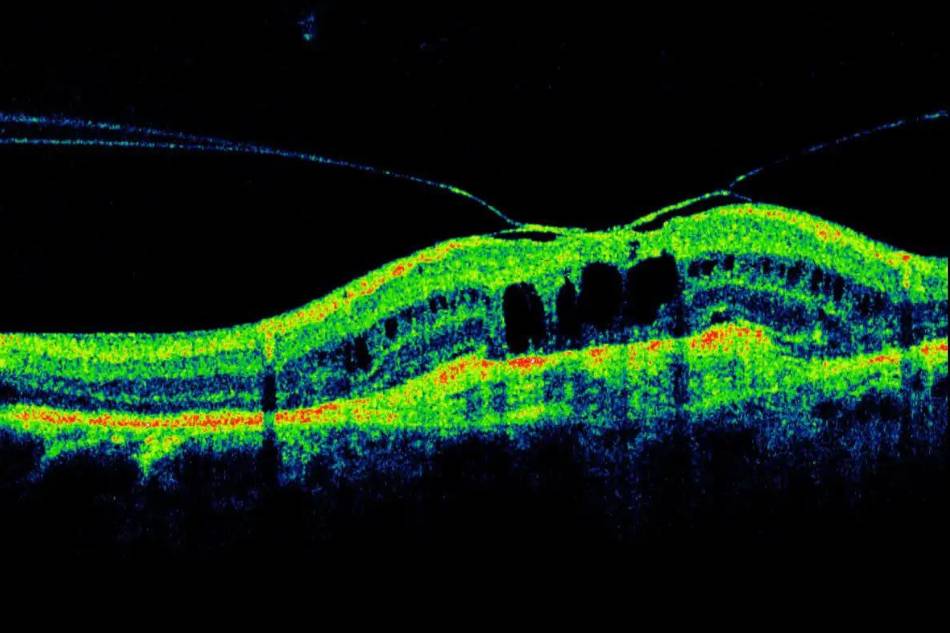

Oculistica: quando l’innovazione tecnologica fa la differenza

OCT: l'innovazione in campo oculistico Nell’ultimo decennio l’evoluzione della ricerca scientifica in ambito oculistico, ha prodotto una sempre più rapida innovazione tecnologica (nuovi strumenti diagnostici, biotecnologie, nanotecnologie, ecc.) che ha garantito maggior precisione nelle diagnosi [...]